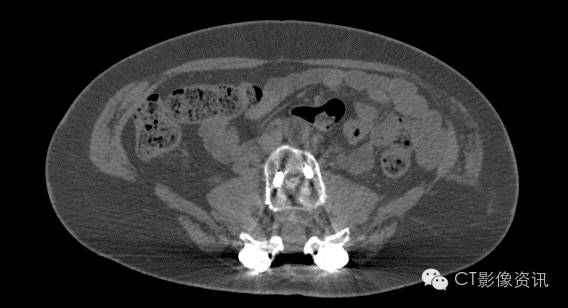

前列腺粒子植入术后

Without MAR

With MAR

Smart MAR 有效地消除掉由于光子饥饿效应带来的白色放射状伪影.